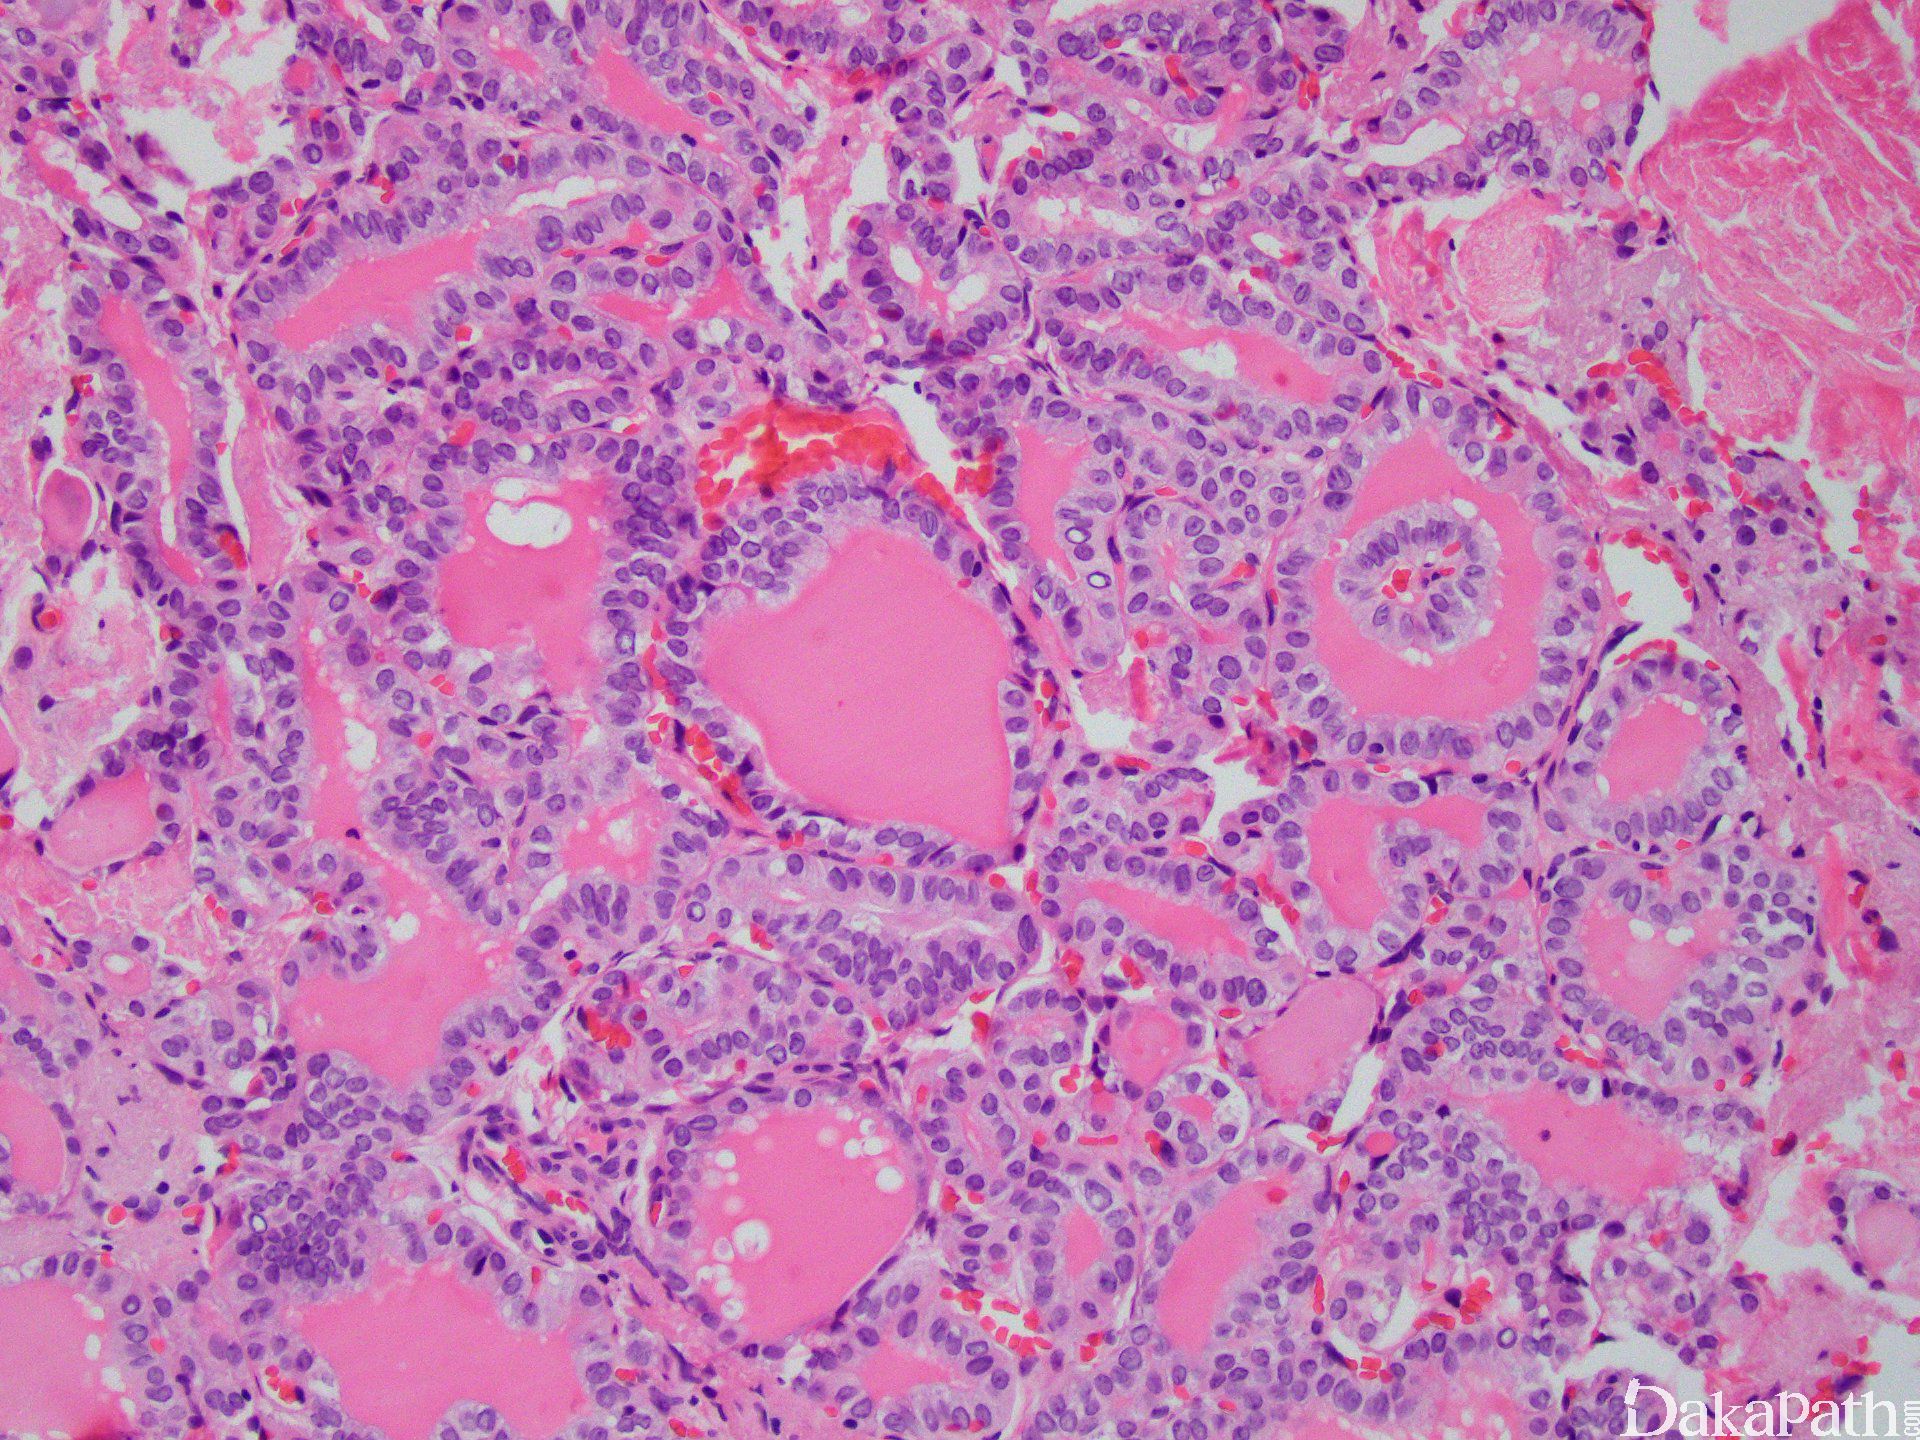

甲状腺滤泡型乳头状癌

Thyroid Papillary Carcinoma,Follicular Variant

约 1/3 病例有包膜;

由小至中等大小、不规则形滤泡构成,滤泡中可见多少不定的胶质,呈强嗜酸性,扇面状;

形成滤泡的大多数上皮细胞含有大而透亮的核,并含核沟和核内假包涵体;

少数病例滤泡内可见到多核巨细胞;

偶见间质硬化和砂砾体;